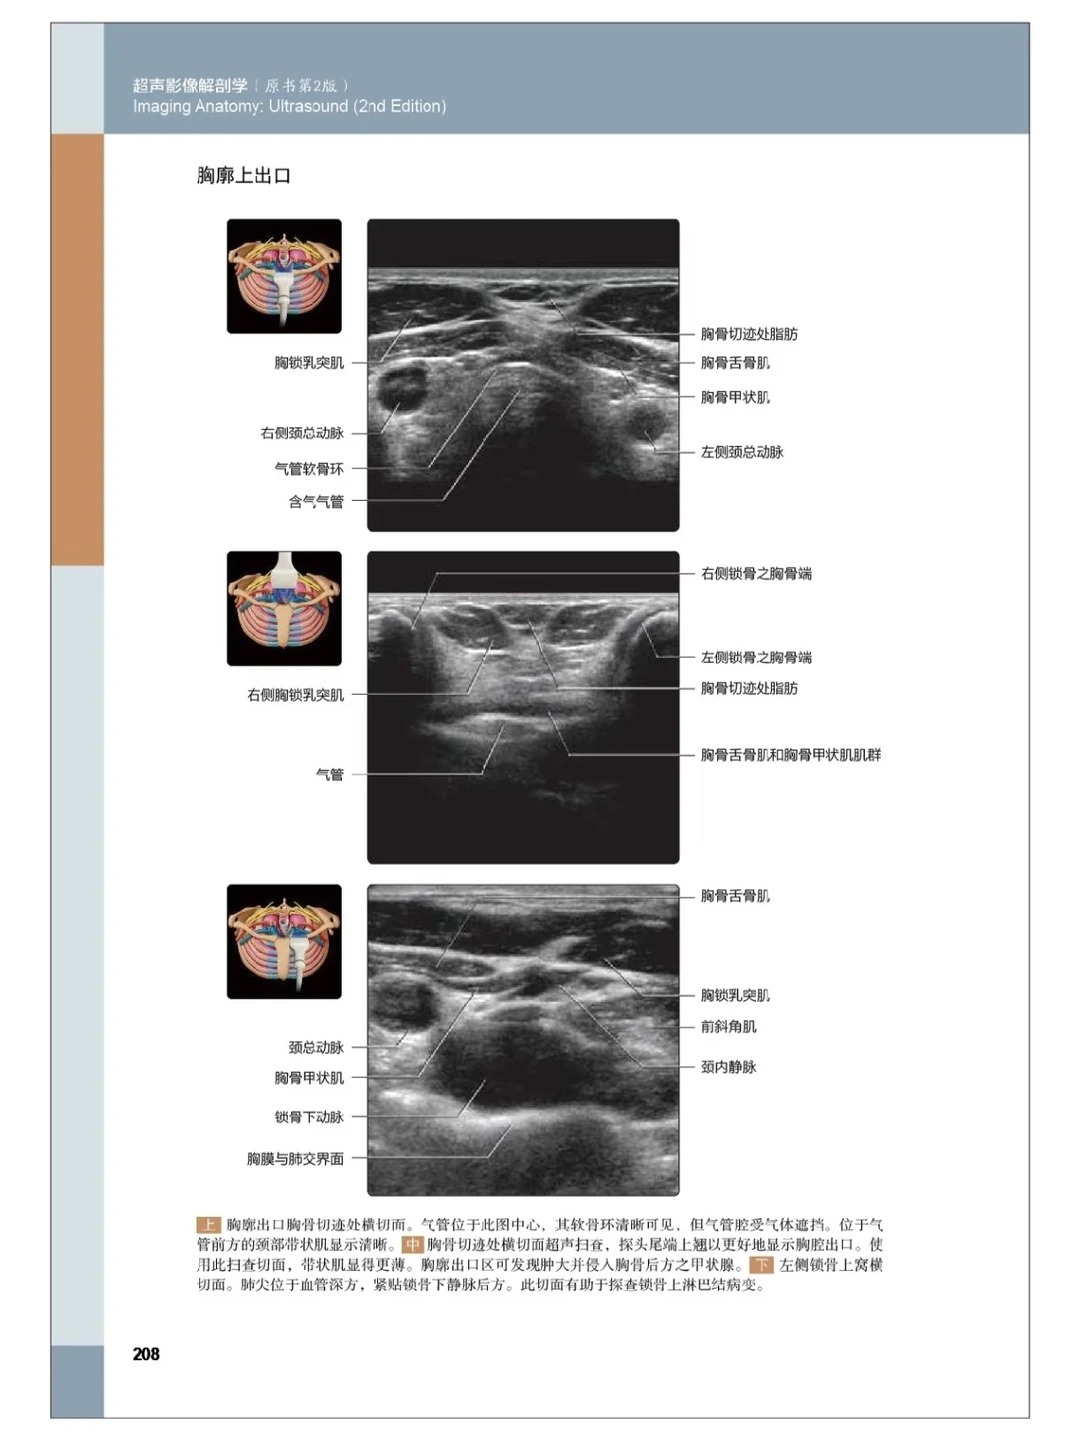

• 图文对照实操篇:上千张高清大体解剖示意图与超声图像左右对照,直观呈现解剖结构与超声影像的对应关系,左边讲解解剖形态,右边标注超声影像特征,手把手教你“看懂超声图”,实现理论与实操无缝衔接,告别死记硬背,提升学习与临床效率;